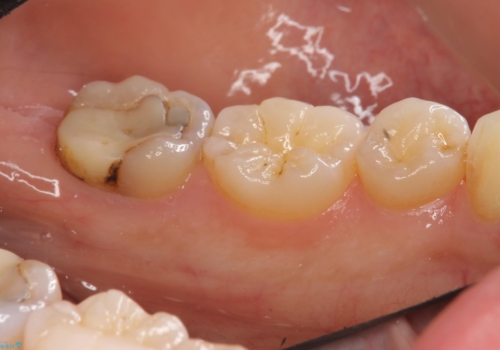

- 左下の7番の虫歯がしみるとのことで来院。

昔他院で虫歯治療した際、「次に虫歯になったらもうきちんとは治せない」と言われたとのことでした。

他院でつめていたものは、セメントで、一時的な詰め物がなされていました。(中は虫歯になっていました。)

虫歯を取ると、歯ぐきの奥深くまで虫歯になっており、そのままではきちんと修復することが難しい状態でした。